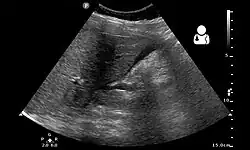

Ultrassom mostrando uma gravidez heterotópica (gravidez intrauterina + extrauterina) com sinais de ruptura da gravidez extrauterina (ectópica).[1]

O padrão-ouro para diagnosticar uma gravidez heterotópica é a ultrassonografia transvaginal. No entanto, a sensibilidade da ultrassonografia transvaginal para esse diagnóstico varia entre 26,3% e 92,4%.[5] Portanto, tanto os sintomas clínicos quanto a imagem ultrassonográfica são usados para o diagnóstico.